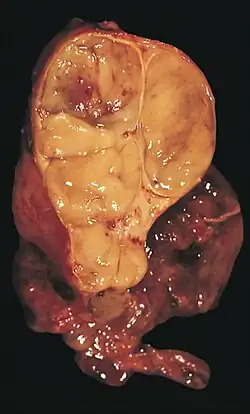

| An encapsulated thymoma (mixed lymphocytic and epithelial type) | |

An encapsulated cystic thymoma. -